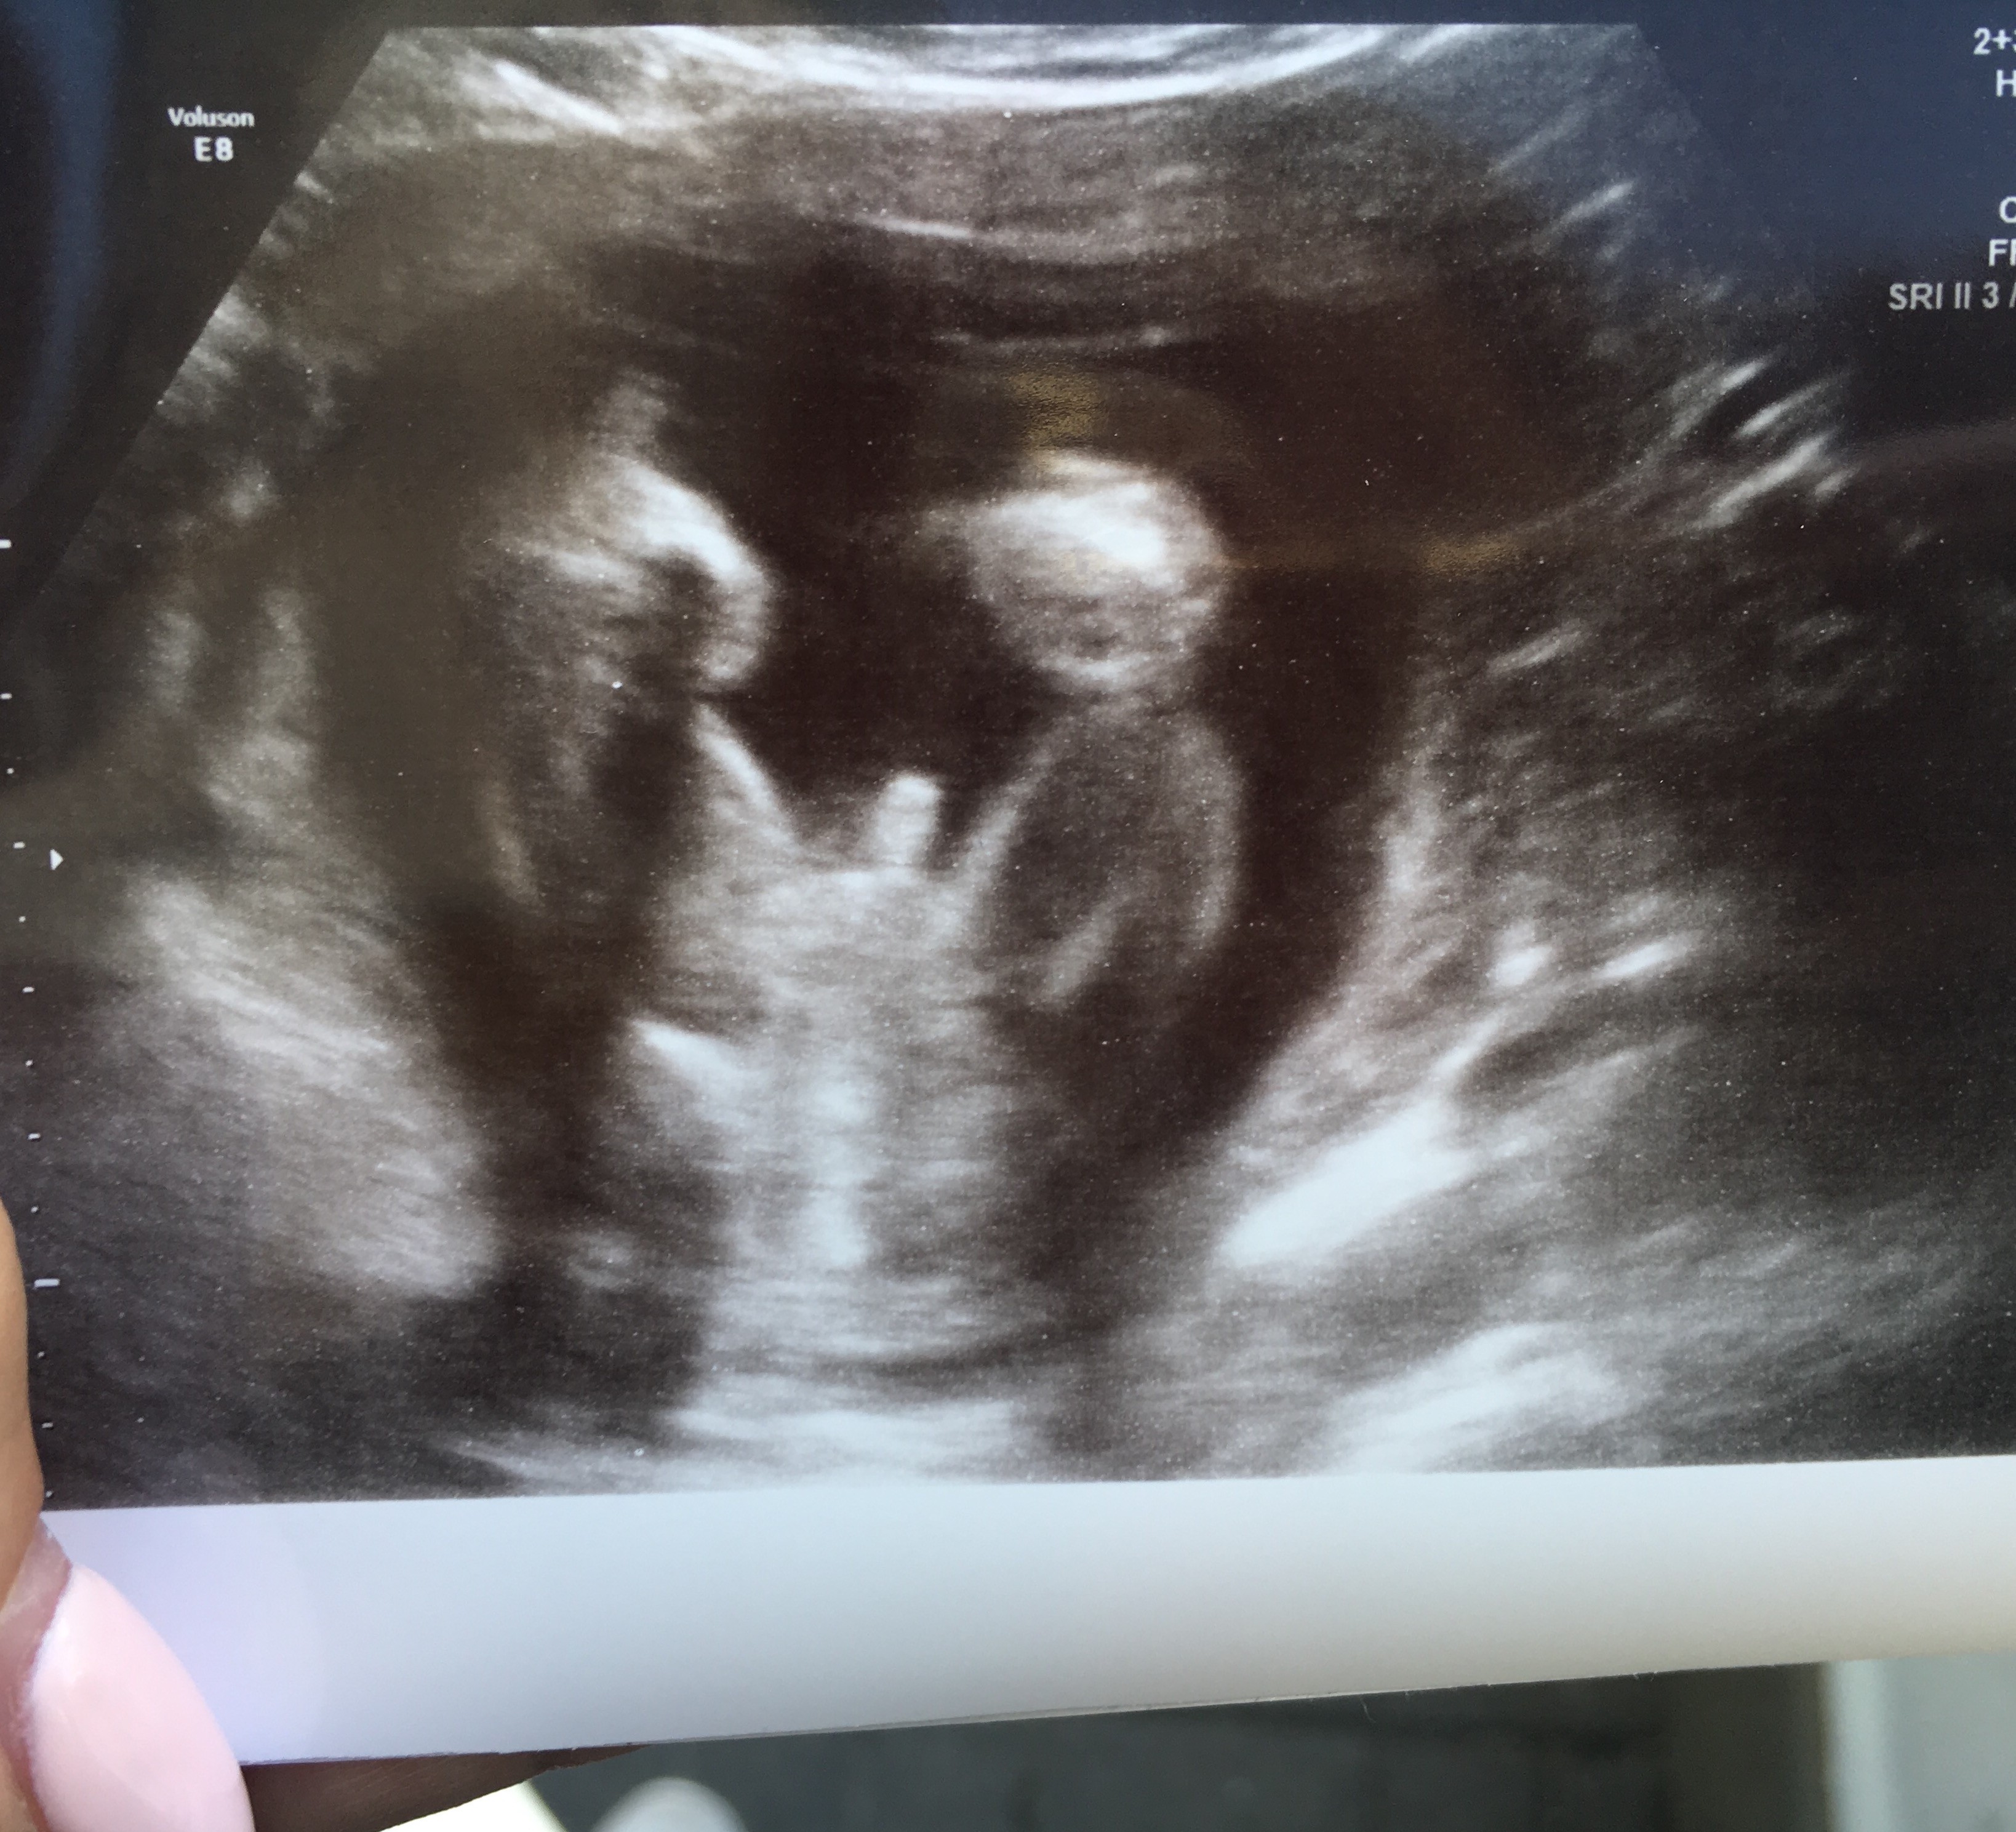

Witam w 19 tygodniu ciąży dowiedziałam się ze będę miała dziewczynkę w 20 tyg okazało się jednak , że to chłopak. Sama już nie wiem bo na jednym usg widać na pewno dziewuche a na drugim chłopca. Może to pempowina ?? Może ktoś mi pomoże rozwiązać ta zagadkę